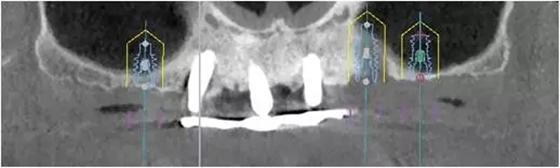

患者男性,51歲,全口無牙,下頜骨量尚可,上頜后牙區(qū)上頜竇底剩余骨高度嚴(yán)重不足,前牙區(qū)牙槽突較豐滿,主訴希望全口種植固定義齒修復(fù)。于2015年 9月接受種植治療:上頜采用All-on-4種植方案、下頜采用常規(guī)種植6顆種植體方案,種植后行即刻修復(fù)(圖1-2)。

1、在25區(qū)補種1顆傾斜種植體,恢復(fù)ALL-on-4修復(fù)方案。造成之前種植體失敗的原因與其受力有關(guān),可能來自于修復(fù)體的咬合設(shè)計,也可能源于上、下頜種植體數(shù)量上的差異(通常上頜種植體數(shù)量應(yīng)多于下頜)。另外,放射學(xué)檢查顯示,15區(qū)種植體邊緣骨吸收較明顯,也提示存在支撐力不足的問題。后來追問病史,該患者修復(fù)后有夜磨牙情況,這進一步證實了上述判斷。鑒于此,這個方案暫不做考慮。2、增加上頜種植體數(shù)量,分別與16、25、26植入3顆,行6顆種植體支撐的常規(guī)種植固定義齒修復(fù)(圖7)。16、25、26區(qū)剩余骨高度嚴(yán)重不足是該方案的不利方面,存在因需要上頜竇底提升手術(shù)所帶來的相應(yīng)手術(shù)風(fēng)險。但是,上頜竇底提升術(shù)是一個成熟、可靠的技術(shù)方法,經(jīng)過與患者充分溝通,最終選擇了這一方案。

1、開窗法雙側(cè)上頜竇底提升術(shù),聯(lián)合25區(qū)植骨術(shù);2、6個月后延期種植,分別與16、25、26植入3顆種植體(如圖7所示);為什么選擇開窗法上頜竇底提升延期種植手術(shù)方案?上頜竇底提升同期種植的標(biāo)準(zhǔn)是植入種植體能夠獲得初期穩(wěn)定性,竇底植骨材料不具有增加種植體穩(wěn)定性的作用,共識性意見認(rèn)為剩余骨高度一般應(yīng)大于4-5mm。開窗法是骨高度嚴(yán)重不足進行上頜竇底提升的有效和可靠術(shù)式。當(dāng)然,國際上也有關(guān)于采用沖壓法提升剩余骨高度僅有1-2mm上頜竇底的成功病例報道,但是目前尚缺乏大樣本、多中心重復(fù)性的臨床研究證明,還沒有得到廣泛的國際共識,不易作為常規(guī)術(shù)式,有待未來進一步的研究。為什么有越來越多種植體掉入上頜竇內(nèi)的病例發(fā)生?這是一個應(yīng)該盡量杜絕的并發(fā)癥,即使臨床發(fā)生率并不高。盲目擴大同期種植適應(yīng)證、種植體無初期穩(wěn)定性是其主要原因。北一種植老師總結(jié):無論種植技術(shù)如何發(fā)展,如何進步。作為一名種植醫(yī)生掌握上頜竇外提升手術(shù)及內(nèi)提升手術(shù)是一項基本功。 因此需要所有醫(yī)生熟練掌握,應(yīng)對各種并發(fā)癥大有幫助。